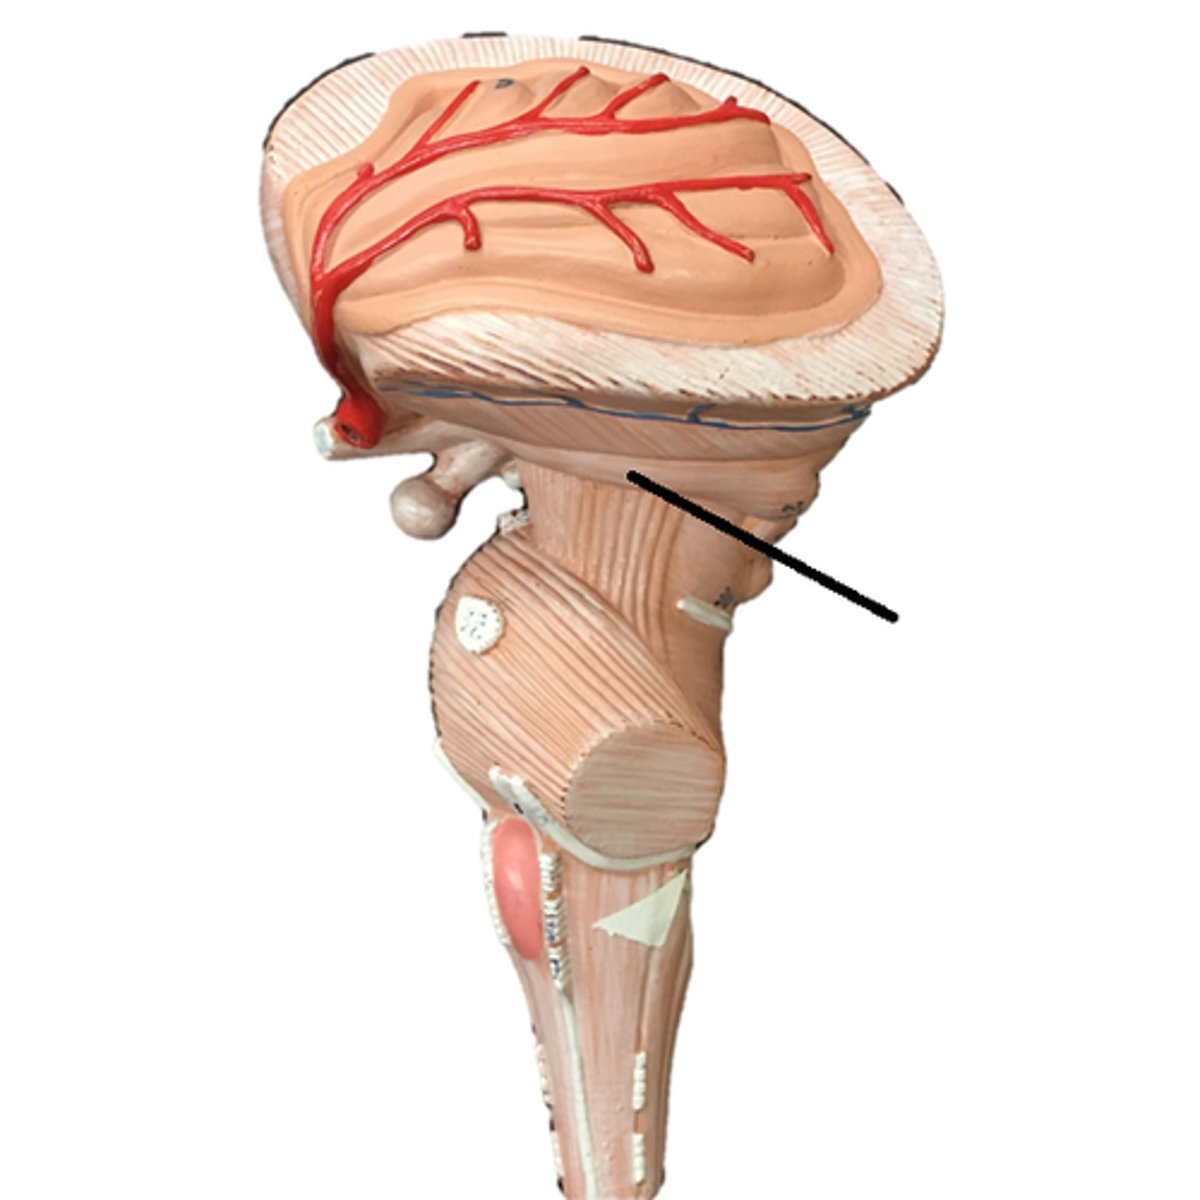

pons

medulla oblongata

olive

cerebral peduncles

Cerebellum

cerebellar peduncles

arbor vitae